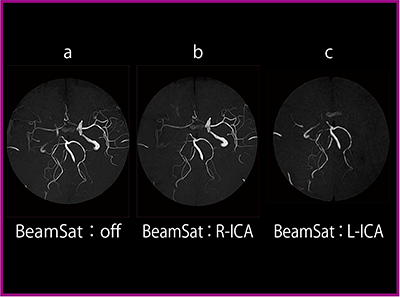

●BeamSat TOF

MRAの血管描出法である3D TOFは,側副血行路による血流など複雑な血行動態の描出が難しいという欠点があった。ECHELON OVALに搭載されたBeam

Sat TOFは,特定血管の信号を抑制して3D TOFと併用することで,頭部の複雑な血行動態を非造影で描出することができる。

直径30mmのペンシルビーム型プリサチュレーションパルス(BeamSatパルス)を印加することにより,目的血管の走行に沿った選択的信号抑制が可能である。抑制領域は目的血管に対して局所的であるため,椎骨動脈(VA)や中大脳動脈(MCA)など近傍血管の描出への影響が少ない。

(2)症例提示

症例(44歳,男性)は,右内頸動脈(R-ICA)狭窄に対する外来内服加療中に左半身麻痺を生じ,SPECTでR-ICA狭窄による一過性脳虚血発作と診断された。そこで,右浅側頭動脈(R-STA)-右中大脳動脈(R-MCA)バイパス手術予定となった。

術前MRAのMIP画像のBeamSatなし(図5 a)では,R-ICAに狭窄所見はあるものの,R-MCAはわずかに描出される。R-ICAにBeamSatを印加すると,R-MCAが左内頸動脈(L-ICA)系からウィリス動脈輪を介して描出されていることがわかる(図5 b)。L-ICAにBeamSatを印加すると,R-MCAを含めたウィリス動脈輪より末梢の血管が描出されないことから,ウィリス動脈輪の血流はL-ICAに頼っていることがわかる(図5 c)。

また,血管造影との比較では,R-ICAにBeamSatを印加した画像とL-ICA造影画像は,ウィリス動脈輪より末梢の血流が同じように描出された。なお,L-ICAにBeamSatを印加した画像とR-ICA造影画像は,共にR-ICA狭窄が認められたが,前者では椎骨脳底動脈系から後交通動脈を介してR-MCAの描出を確認できたのに対し,後者では判断できなかった。

図5 術前MRAのMIP画像

(3)考察

BeamSat TOFは,片側の内頸動脈狭窄・閉塞に伴う対側からの血行動態の描出において,造影画像と同等の情報が得られ,治療方針の決定や術後の経過観察に有用であると考えられる。動脈の高度蛇行症例や両側の内頸動脈狭窄・閉塞症例では,ウィリス動脈輪の描出が困難なため適応症例は限られるが,非侵襲的に外来検査が可能なBeamSat TOFの臨床的有用性は高いと言える。今後は症例を重ね,撮像時間の短縮をめざして検討を進めていく。